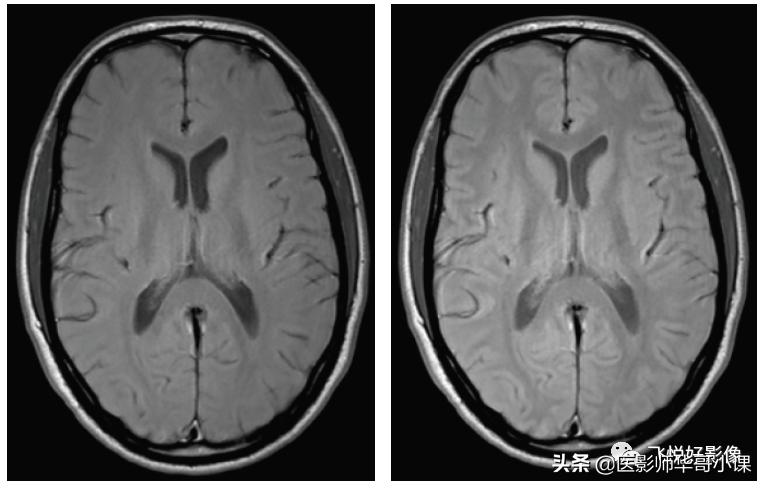

我们通过磁共振脑实质成像,来表现不同加权图像的信号对比特点,通过短TR、短TE实现T1加权成像;通过长TR、长TE实现T2加权成像(由于SE采集效率低,在实现T2加权中,可利用快速自旋回波序列TSE代替);通过长TR、短TE实现PD加权成像。

图4,TSE PD加权图像。横断面脑实质PD加权图像,左图TR=1500ms,TE=20ms,右图TR=2000ms,TE=20ms。PD加权图像主要反映组织的质子密度,在长TR时间条件上,纵向弛豫已完全恢复,在短TE时间条件下,横向弛豫衰减不明显,因而在长TR、短TE时,图像信号强度反映的是组织质子密度。PD加权图像解剖结构的显示不如T1加权图像,脑灰质相对于脑白质相对呈中高信号,脑脊液信号与脑灰质类似,脂肪组织仍显示为高信号,而骨结构、空气等在磁共振中不产生信号。(图像源自飞利浦磁共振系统)